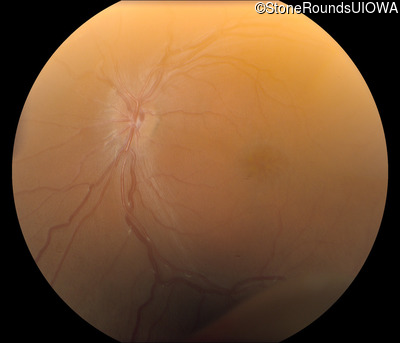

Fundus Photography - Right - 10/40

Exemplar